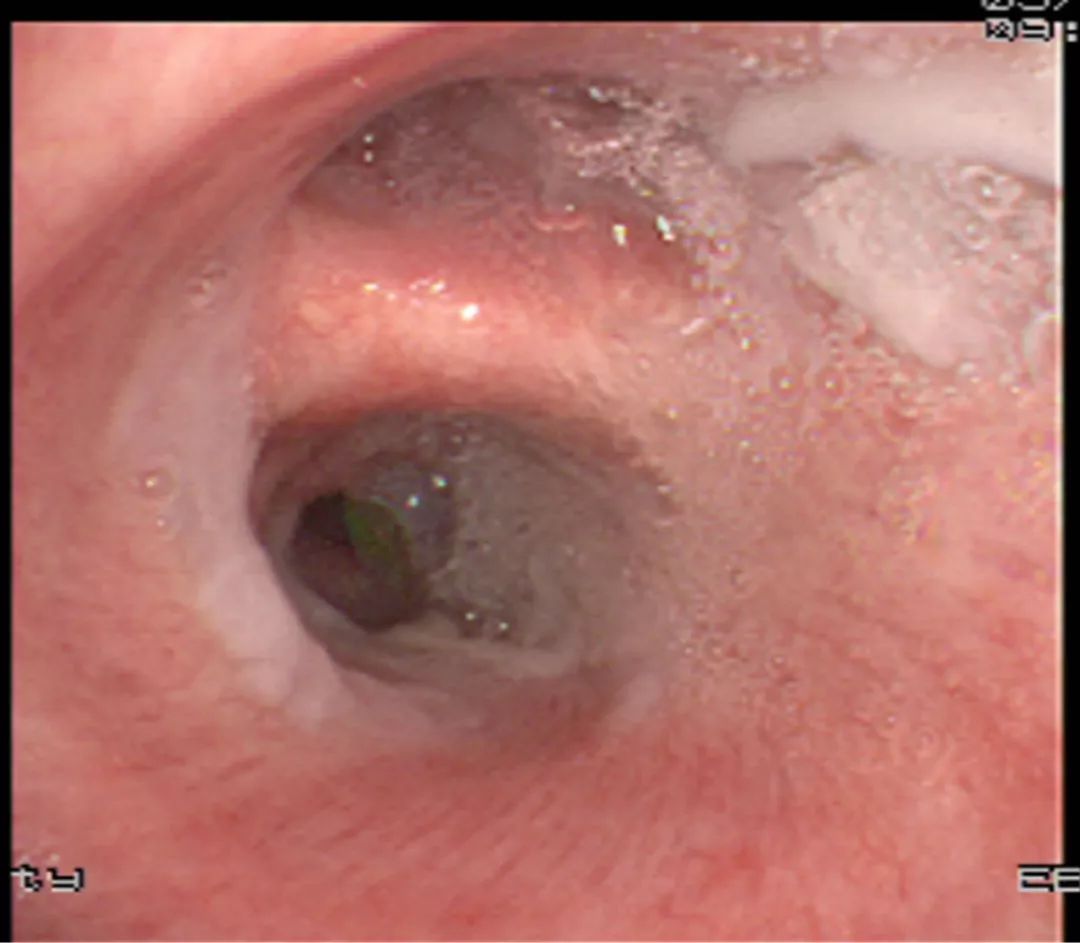

电子支气管镜显支气管黏膜充血、右侧主气道上的厚黄白色粘液栓